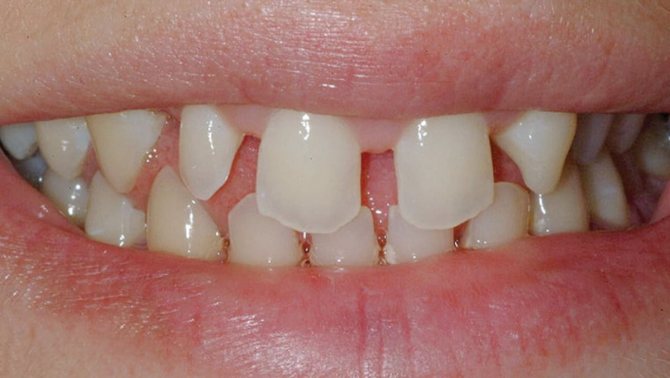

Аномалии положения зубов

Это самые тяжелые и серьезные отклонения. При такой аномалии, зубы обычно занимают неправильное положение, причем происходит это не только вне зубного ряда, но и внутри него. Различают сразу несколько видов неправильного положения зубов:

- Дистальное положение. В этом случае зуб сильно смещается назад из зубного ряда.

- Мезиальное положение. В этом случае зубы, наоборот, сильно выпадают вперед.

- Вестибулярное положение. Так говорят в том случае, когда зубы располагаются близко к губам или щекам, в зависимости от их вида.

- Оральное положение. В данном случае практически все зубы сильно смещаются вглубь полости рта.

- Супраположение. Здесь зубы могут быть расположены аномально выше окклюзионной кривой, а также значительно ниже нее, но в этом случае аномалия получит название – инфраположение.

- Тортоаномалия. Один или несколько зубов могут быть развернуты вдоль вертикальной оси. Если некоторые зубы меняются местами, то это называется транспозицией.

Устранить все эти аномалии может врач-ортодонт. Сделать это не так сложно. Современные брекет-системы и ортодонтические аппараты творят настоящие чудеса за короткое время.